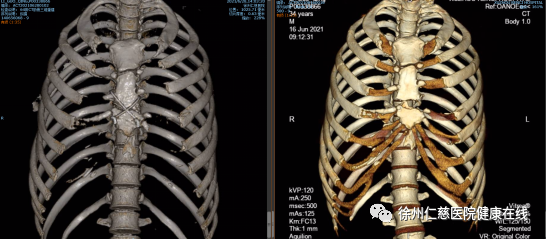

王保毅主任的手术团队为李师傅进行了「开胸探查+心包开窗术+胸骨骨折内固定+肋骨骨折内固定」的手术,术中首先清除心包内的积气,然后针对胸骨和肋骨骨折进行内固定。在医生近两小时的努力下,李师傅成功脱离危险。

术前术后胸骨对比图

术前术后心包积气情况对比